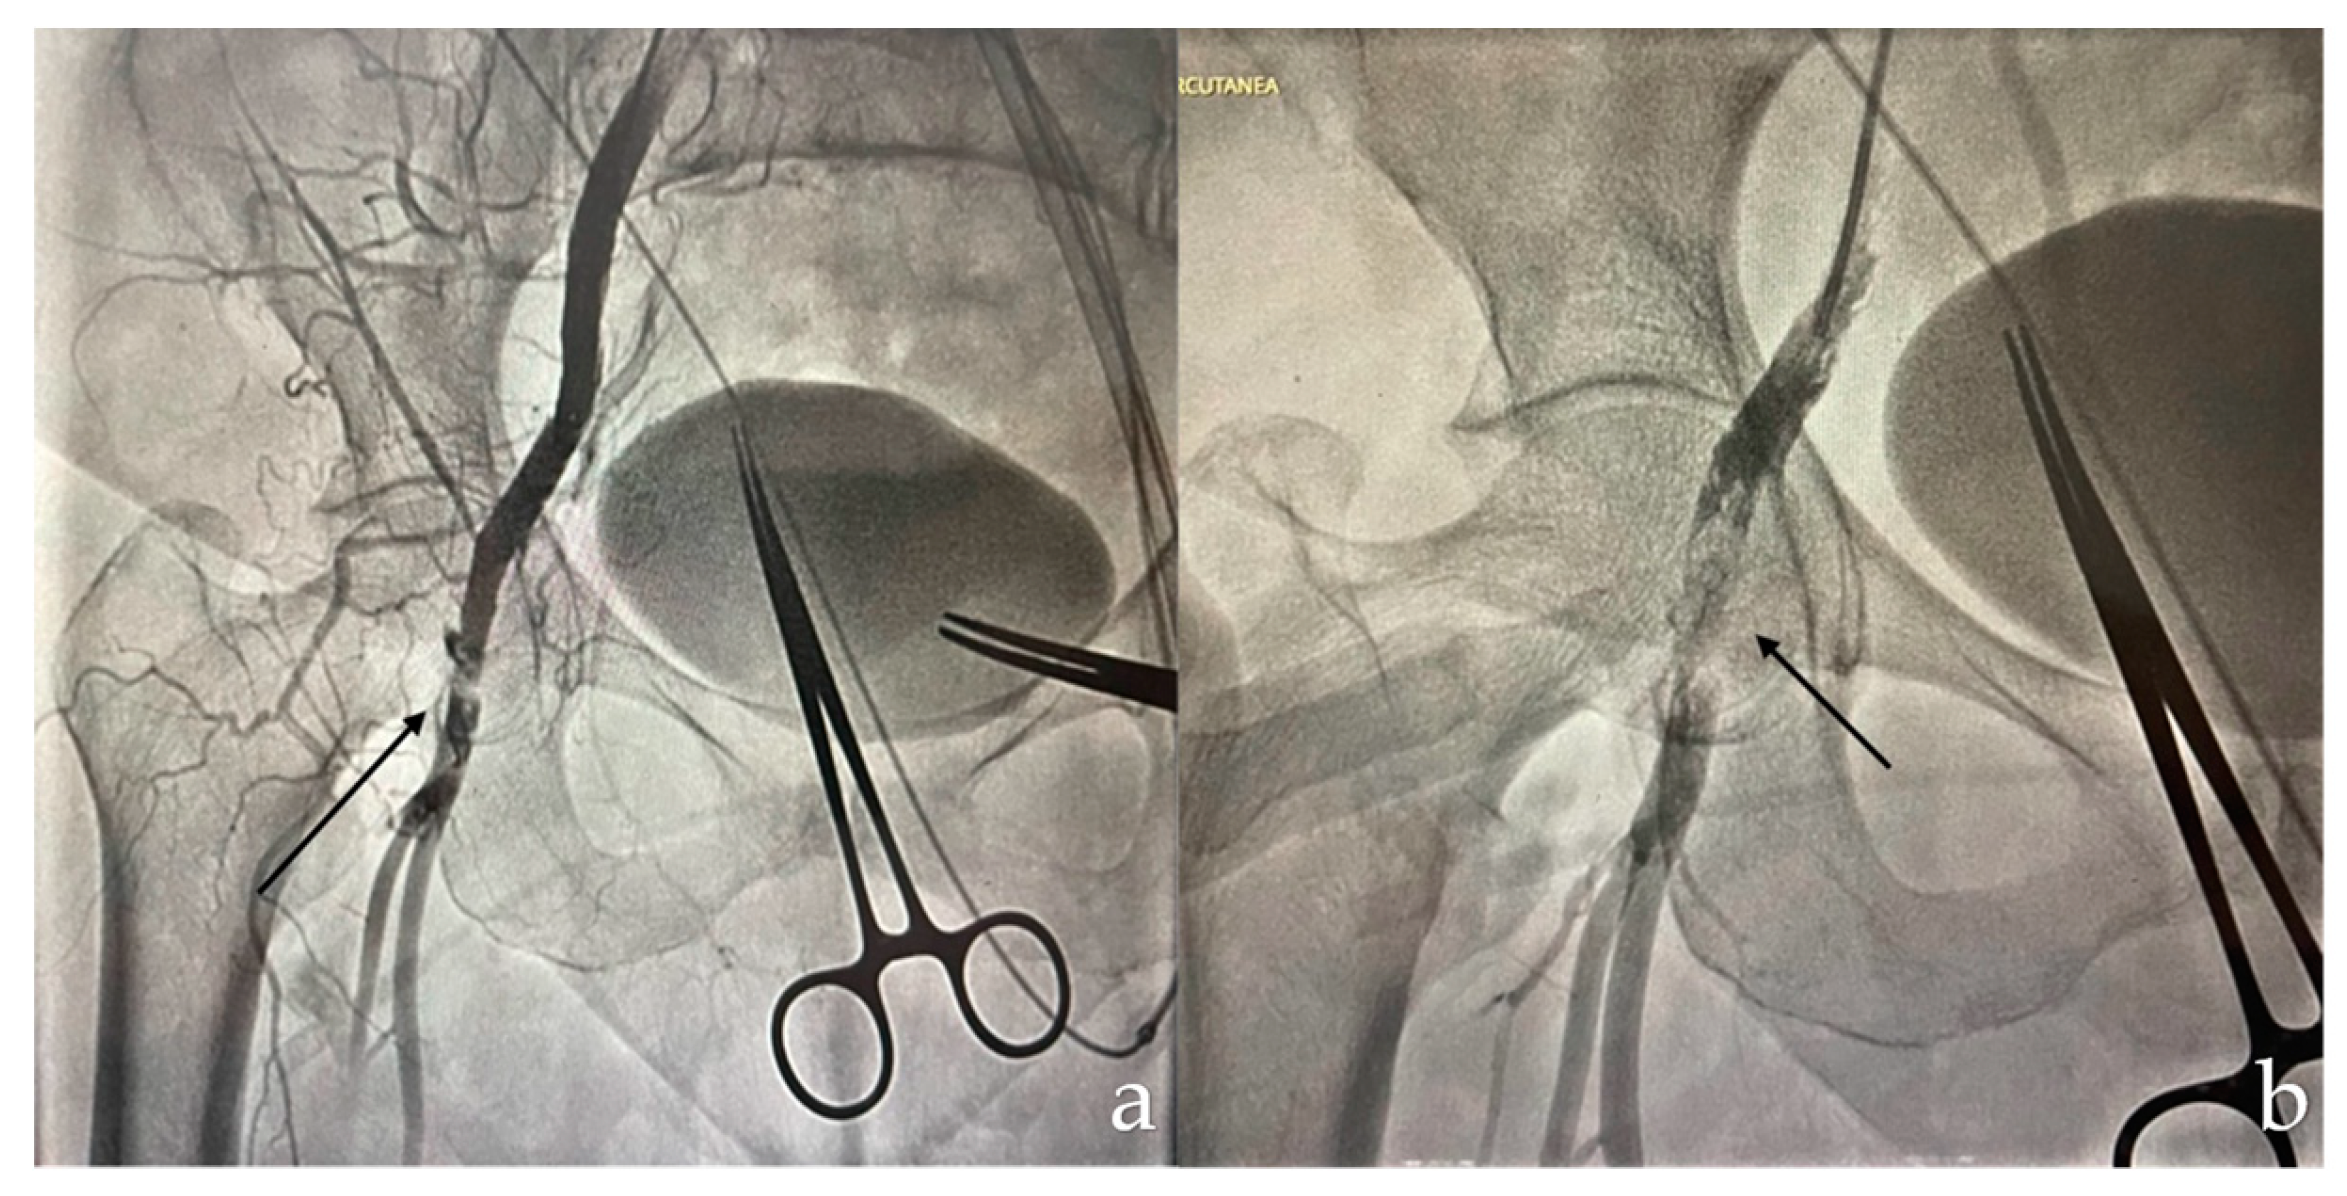

A 68-year-old patient with a history of open surgery for aortic and mitral valve replacement, in addition to coronary revascularization with bypass, presented severe aortic valve stenosis requiring TAVI. During the procedure, the patient experienced acute limb ischemia due to occlusion of the right common femoral artery after use of the ProGlide™ device (Abbott), requiring femoral stent placement (Figure 1).

Iliac artery dissections can occur during the passage of wires or devices. It is crucial to identify and adequately treat these dissections, even if they do not cause significant clinical problems during the procedure. We recommend a final angiography of the iliac arteries. The usual treatment consists of implanting bare nitinol stents, or covered stents if thrombus formation is suspected. On the other hand, common femoral artery occlusions often occur following the use of vascular closure devices, especially when needle-based systems such as Perclose ProGlide™ (Abbott) are used in combination with collagen-based systems such as AngioSeal (Terumo, Japan). In addition, advancement of large lumen devices can dislodge plaques and lead to occlusion of the vessel lumen. This occlusion presents as acute or subacute ischemia, which should be identified before the patient leaves the catheterization laboratory. Clinical monitoring of the foot of the punctured leg and Doppler ultrasound the following day are crucial.

Figure 1. (a) Femoral artery occlusion (b) Femoral artery stent placement.